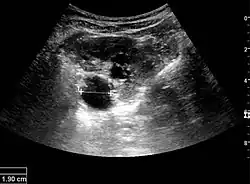

Figure 8. Cortical solid mass, which later was shown to be renal cell carcinoma. Measurement of the solid mass on the US image is illustrated by '+' and a dashed line.[1]

A solid renal mass appears in the US exam with internal echoes, without the well-defined, smooth walls seen in cysts, often with Doppler signal, and is frequently malignant or has a high malignant potential. The most common malignant renal parenchymal tumor is renal cell carcinoma (RCC), which accounts for 86% of the malignancies in the kidney. RCCs are typically isoechoic and peripherally located in the parenchyma, but can be both hypo- and hyper-echoic and are found centrally in medulla or sinus. The lesions can be multifocal and have cystic elements due to necrosis, calcifications and be multifocal (Figure 8 and Figure 9). RCC is associated with von Hippel–Lindau disease, and with tuberous sclerosis, and US has been recommended as a tool for assessment and follow-up of renal masses in these patients.[1]